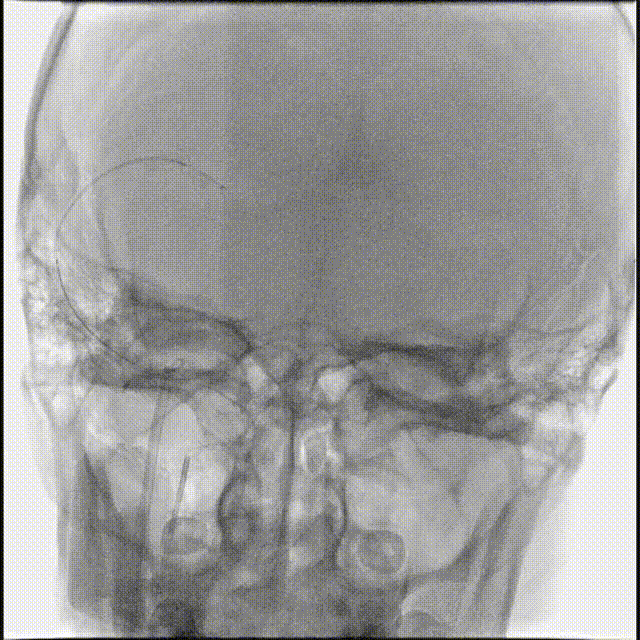

术前CTA/CTP检查,动脉成像未见明显异常,平扫CT可见右侧横窦区域高密度、左侧顶叶片状高密度,窦汇区域、上矢状窦区域高密度充盈。随后紧急性头颅MRV检查,MRV提示上矢状窦及右侧横窦区域不显影。

图注1:1A/1B 平扫CT可见右侧横窦、窦汇区域高密度,额顶叶片状高密度灶

1C 通路CTA检查动脉像未见特殊

1D/1E MRV冠状位及侧位可见上矢状窦及右侧横窦消失,左侧横窦乙状窦部分显影